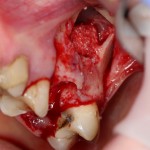

Необходимым условием для проведения этого вмешательства является стадия ремиссии воспалительного процесса в области удаляемого зуба, отсутствие или небольшие размеры очагов хронического воспаления в прикорневой зоне (рис 49, 50, 51):

Рисунок 49, 50, 51. Проведение операции синуслифтинга одномоментно с удалением зуба: слева – скелетирование стенки верхней челюсти, подготовка к удалению зуба, в центре – лунка удаленного зуба (виден небольшой очаг деструкции костной ткани вследствие хронического периодонтита), справа – заполнение субантральной полости спейсером.